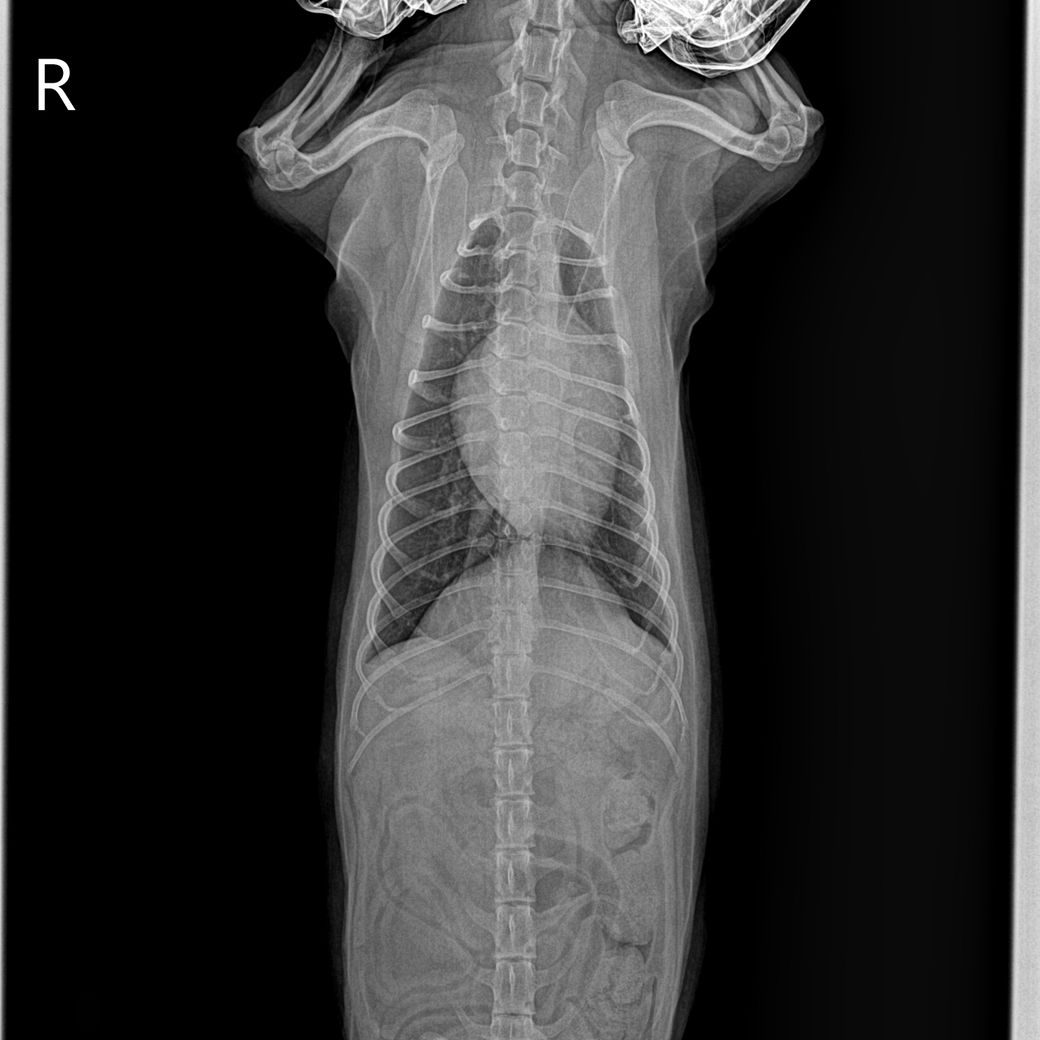

안녕하세요 강아지 건강검진을했는데 흉골이 휘었다고해서요. 첫번째사진은 1년전이고 2,3번째 사진은 이번년도 사진입니다.

혹시 이런경우 원인은 무엇인가요? 외부충격은 없었습니다..

2~3번 사진은 촬영상이 돌아가면서 흉골이 "휘어 보이는것 처럼" 보이는 것이고 실제 휜게 아닙니다. 앞에서 언급되었던 오목가슴과 같은 문제는 이 촬영상이 아닌 옆에서 촬영하는 외측상으로 판단하는것입니다.